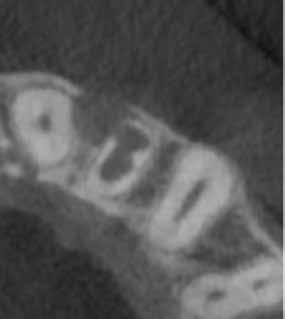

8. a–e ábra: A kiindulási röntgen (a) és a kiindulási állapotról készített CBCT-felvétel (b–e). A felvételen jól látható a csatornafal és a bukkális kortikális perforációja.

8a 8b 8c 8d 8e

perforáció

16. a–b ábrák: A két évvel később készített kontroll CBCT-felvétel. – 17. a–b ábrák: A négy évvel később készített kontroll CBCT-felvétel.